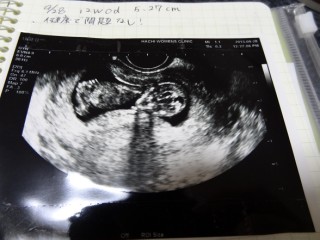

かなり大きくなりびっくりしました。つわりであんまり食べれなくても赤ちゃんは育っていくんだなと思い赤ちゃんの生命力を感じました。

背骨が見えます。前回(9w)の時はよく見えなかったけど、人間らしくなり、より実感がわいてきました。

検診で赤ちゃんに会えるのが楽しみです!

順調に育ってくれてて良かったぁ♪